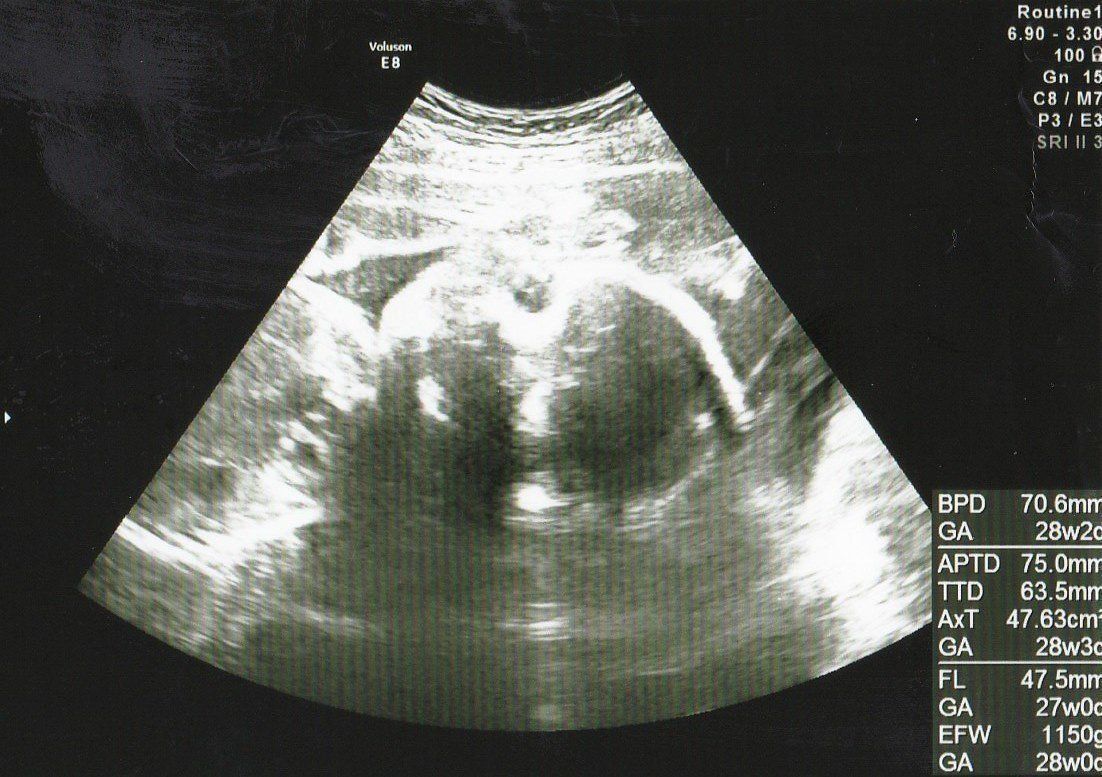

<妊娠後期> 妊娠28~36週。ちょっと大きめな赤ちゃんは生まれる気配なし

妊娠28週目の4Dエコー写真 私のおなかを苦しめる、ちょっと大きめな赤ちゃん

推定体重=1465g

お顔をアップにした4D画像です。うつむき加減で眠っているように見えました。赤ちゃんは順調に大きくなり、これ以降、毎回「ちょっと大きめですね」と言われるようになります。実際、おなかも苦しくなってきて、パソコン作業がつらくなってきました。ちょうど真夏の時期で、外出がとてもつらかったのを覚えています。